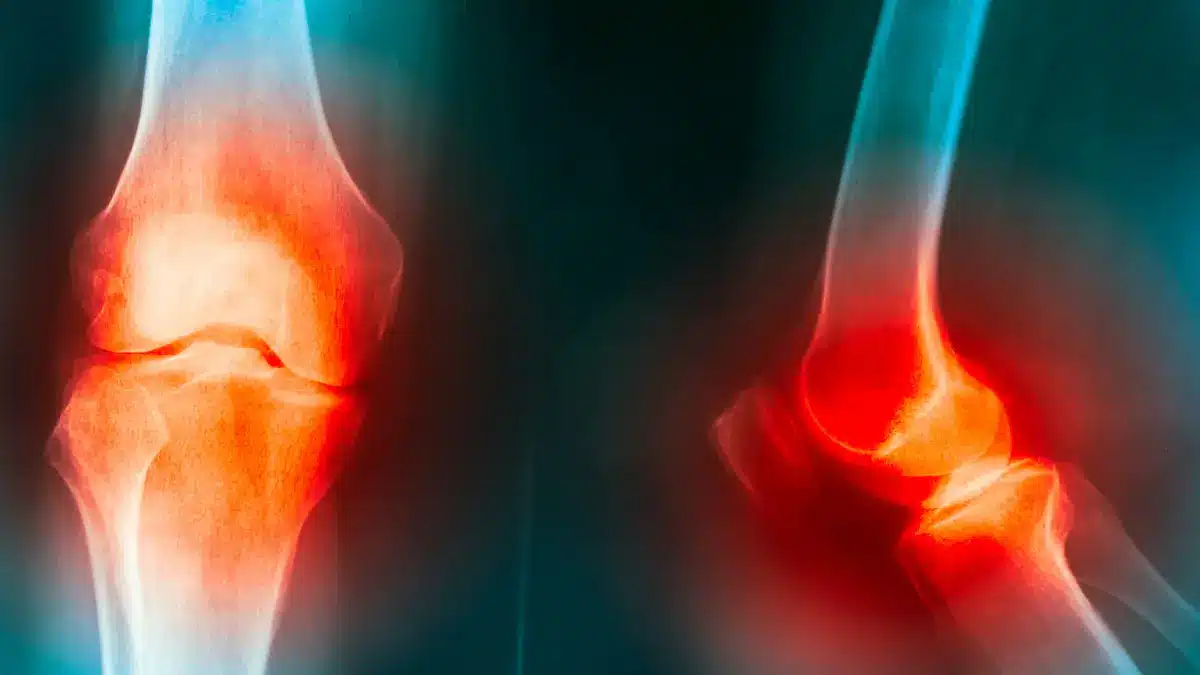

Raio X de Joelho: Para Que Serve e Quando é Indicado?Como ortopedista especializado em joelho, vejo diariamente em meus pacientes a importância do raio X de joelho para um diagnóstico… Leia mais »